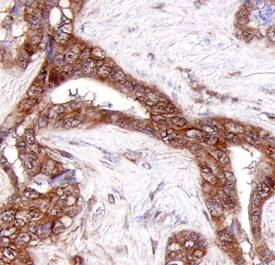

Collagen XXIII a1 antibody in Human Adenocarcinoma by Immunohistochemistry (IHC-P).

Collagen XXIII alpha1 in Human Adenocarcinoma.

Collagen XXIII a1 was detected in immersion fixed paraffin-embedded sections of human adenocarcinoma using Human Collagen XXIII a1 Monoclonal Antibody (Catalog # MAB4165) at 25 µg/mL overnight at 4 °C. Tissue was stained using the Anti-Mouse HRP-DAB Cell & Tissue Staining Kit (brown; Catalog # CTS002) and counterstained with hematoxylin (blue). Specific staining was localized to cytoplasm. View our protocol for Chromogenic IHC Staining of Paraffin-embedded Tissue Sections.

Sample: Immersion fixed paraffin-embedded sections of human adenocarcinoma